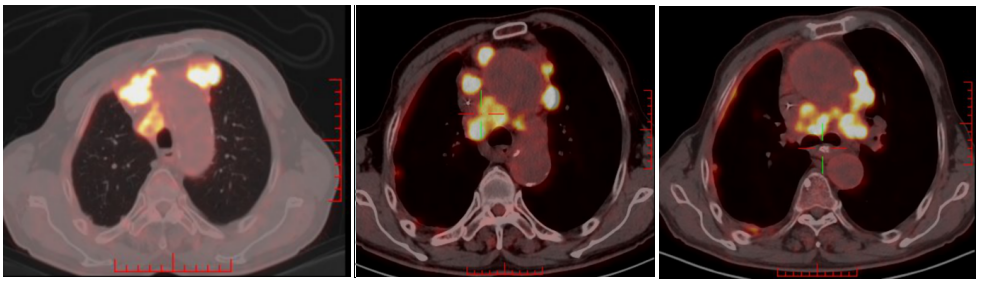

2022-07-01至2022-10-21行6周期斯鲁利单抗300mg d1+白蛋白紫杉醇(260mg/m2)450mg d1+奈达铂(75mg/m2)130mg d1,q21d治疗,同时给予伊班膦酸钠预防骨不良事件。期间因化疗后III度骨髓抑制,第5、6周期白蛋白紫杉醇+奈达铂双药减量10%化疗。

2022-08-15(治疗2周期后)CT、2022-09-28(治疗4周期后)CT、2022-11-08(治疗6周期后)CT:右肺上叶前段软组织密度影逐渐缩小(49mm*27mm→45mm*23mm→44mm*22mm),疗效综合评估SD。